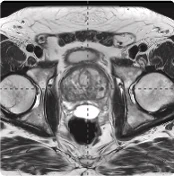

BioProtect 215cc Prostate

215 cc Prostate Post-MRI showing BioProtect Balloon Spacer, prostate, and rectum.

Post-MRI

Image courtesy of Dr. Shawn Zimberg, Radiation Oncologist.